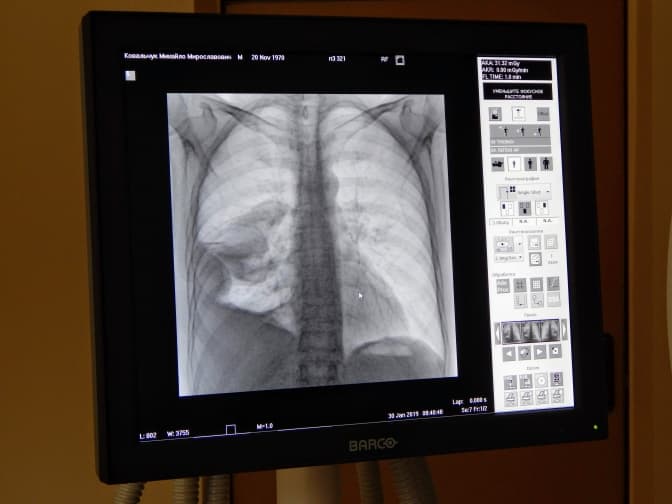

У львівському Центрі легеневого здоров’я, що на вулиці Зеленій, 477, встановили рентген-діагностичну систему Apollo EZ DRF італійського виробництва, що є єдиною в Україні з такою потужністю. Про це Tvoemisto.tv повідомили у ЦЛЗ.

Діагностична система має інноваційні функції томосинтезу, дозволяє виконувати всі типи дослідження у цифровому форматі.

«Вона дозволяє робити радіографію, томографію та флюороскопію. За допомогою системи можна обстежувати всі органи і частини тіла. Вона дає зображення високої якості, деталізує картинку, що більш інформативна, ніж при звичайному обстеженні. Також можна записати відео і показати його потім лікарю, який призначатиме лікування», – розповідають в Центрі.

У медзакладі додають, що система у порівнянні з іншими подібними апаратами дає менше дозове навантаження на пацієнта, а вартість дослідження значно зменшується в порівнянні з КТ.

Фото: Центр легеневого здоров'я